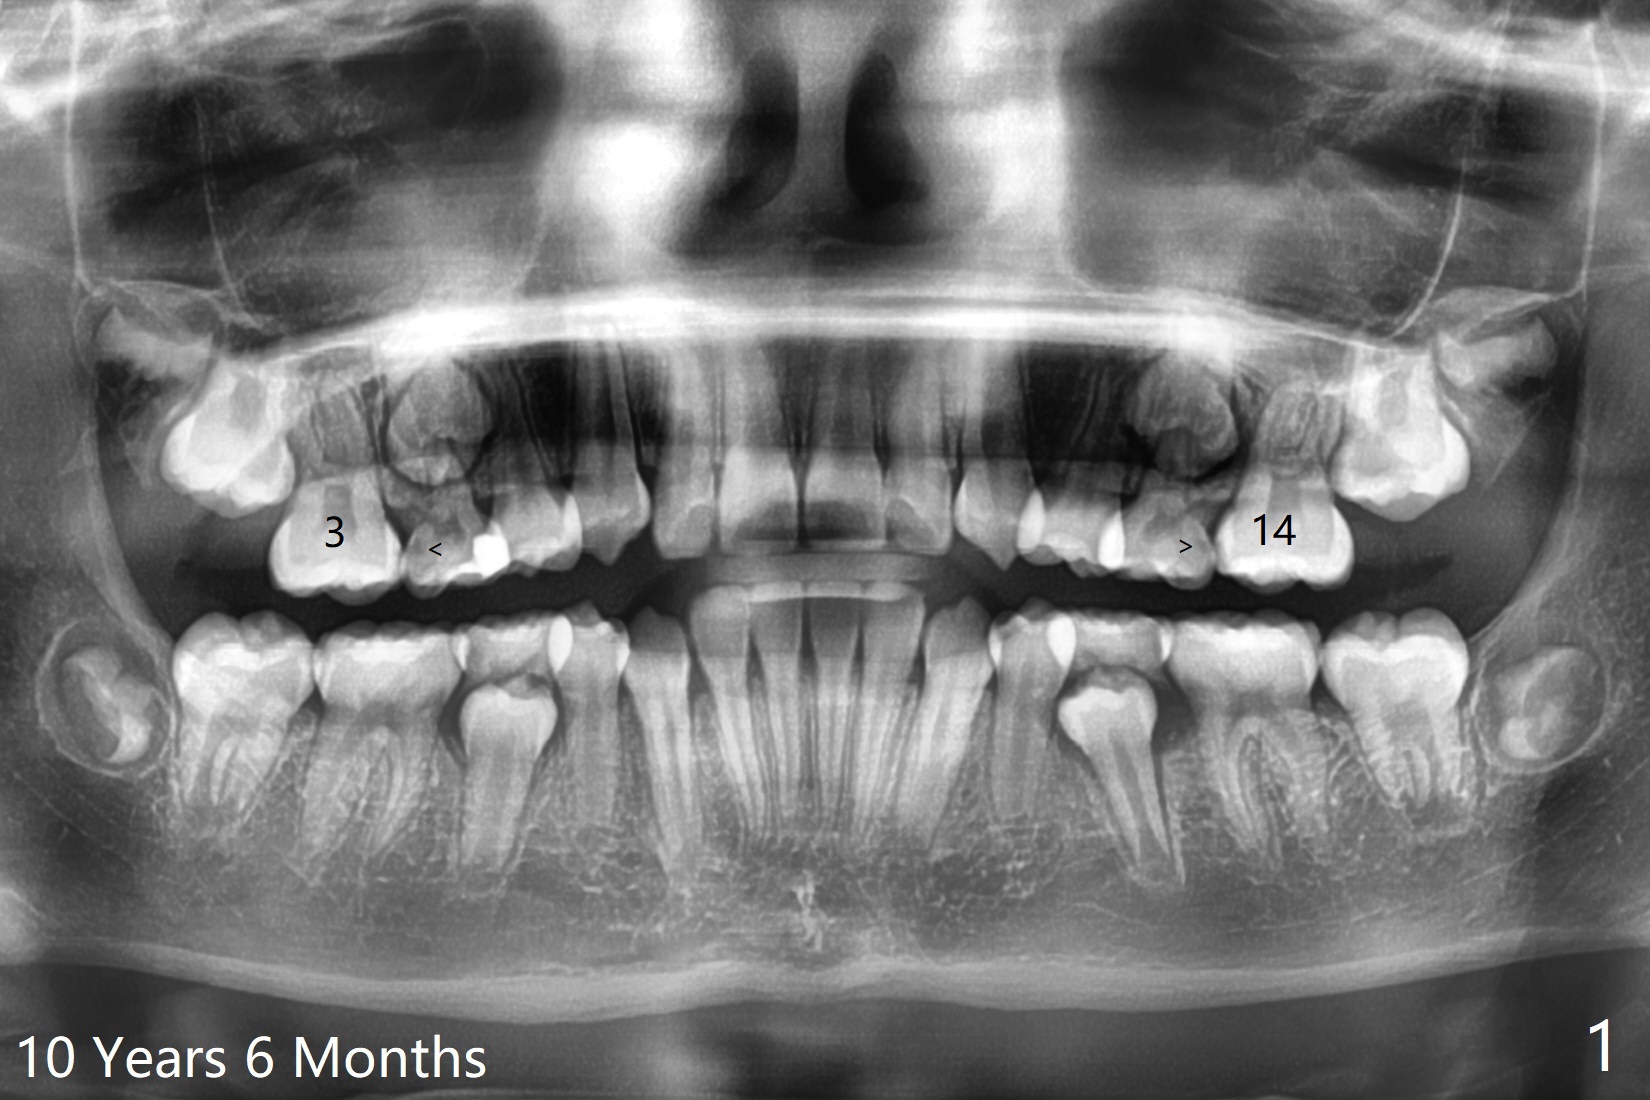

10岁半女孩上颌第二乳磨牙远中龋好像造成第一恒磨牙近中龋(图一)。要求妈妈当乳磨牙脱落时,带她回来补牙。由于新冠病毒,女孩1年3个月后才回来,右上第二前磨牙已经基本完成萌出,右上6近中龋被掩盖了(图二),而左侧前磨牙腭侧部分萌出(图三,四),磨牙近中龋(表现为脱钙,图四:箭头)正好暴露。塞入gingival retraction cord(图五:C)和wedge (W),去龋,填入树脂,两牙之间通过牙线(F),光固化。之后不需要抛光。